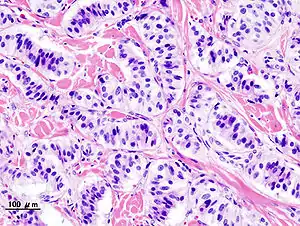

| Pathology of pancreatic endocrine tumor (insulinoma). | |